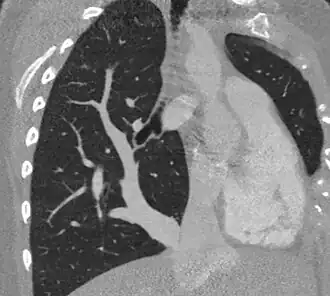

![]() Síndrome de la cimitarra.TAC torácico | ||

El síndrome de la cimitarra, también conocido como síndrome de drenaje venoso anómalo del pulmón derecho, es una enfermedad congénita inusual que consiste en un mal drenaje de las venas pulmonares derechas a la vena cava inferior, aurícula derecha, que con frecuencia se asocia a hipoplasia del pulmón derecho y de la arteria pulmonar derecha. También se han descrito malformaciones bronquiales, dextrocardia e irrigación arterial anómala de la aorta hacia el pulmón derecho.

Así mismo, su imagen radiológica es clave, ya que recuerda a la de un sable turco en la radiografía de tórax simple. Suele estar acompañado por hipoplasia pulmonar derecha y dextrocardia. Su imagen radiológica corresponde a la visualización de un gran vaso venoso (drenaje de las venas pulmonares) anómalo que recorre la silueta cardíaca derecha para drenar en la vena cava inferior por arriba o por debajo del diafragma.